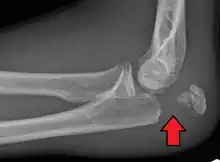

| Fracture of the olecranon | |

Olecranon fracture is a fracture of the bony portion of the elbow. The injury is fairly common and often occurs following a fall or direct trauma to the elbow. The olecranon is the proximal extremity of the ulna which is articulated with the humerus bone and constitutes a part of the elbow articulation. Its location makes it vulnerable to direct trauma.

To assess an olecranon fracture, a careful skin exam is performed to ensure there is no open fracture. Then a complete neurological exam of the upper limb should be documented.[5][2] Frontal and lateral X-ray views of the elbow are typically done to investigate the possibility of an olecranon fracture.[1] A true lateral x-ray is essential to determine the fracture pattern, degree of displacement, comminution, and the degree of articular involvement.